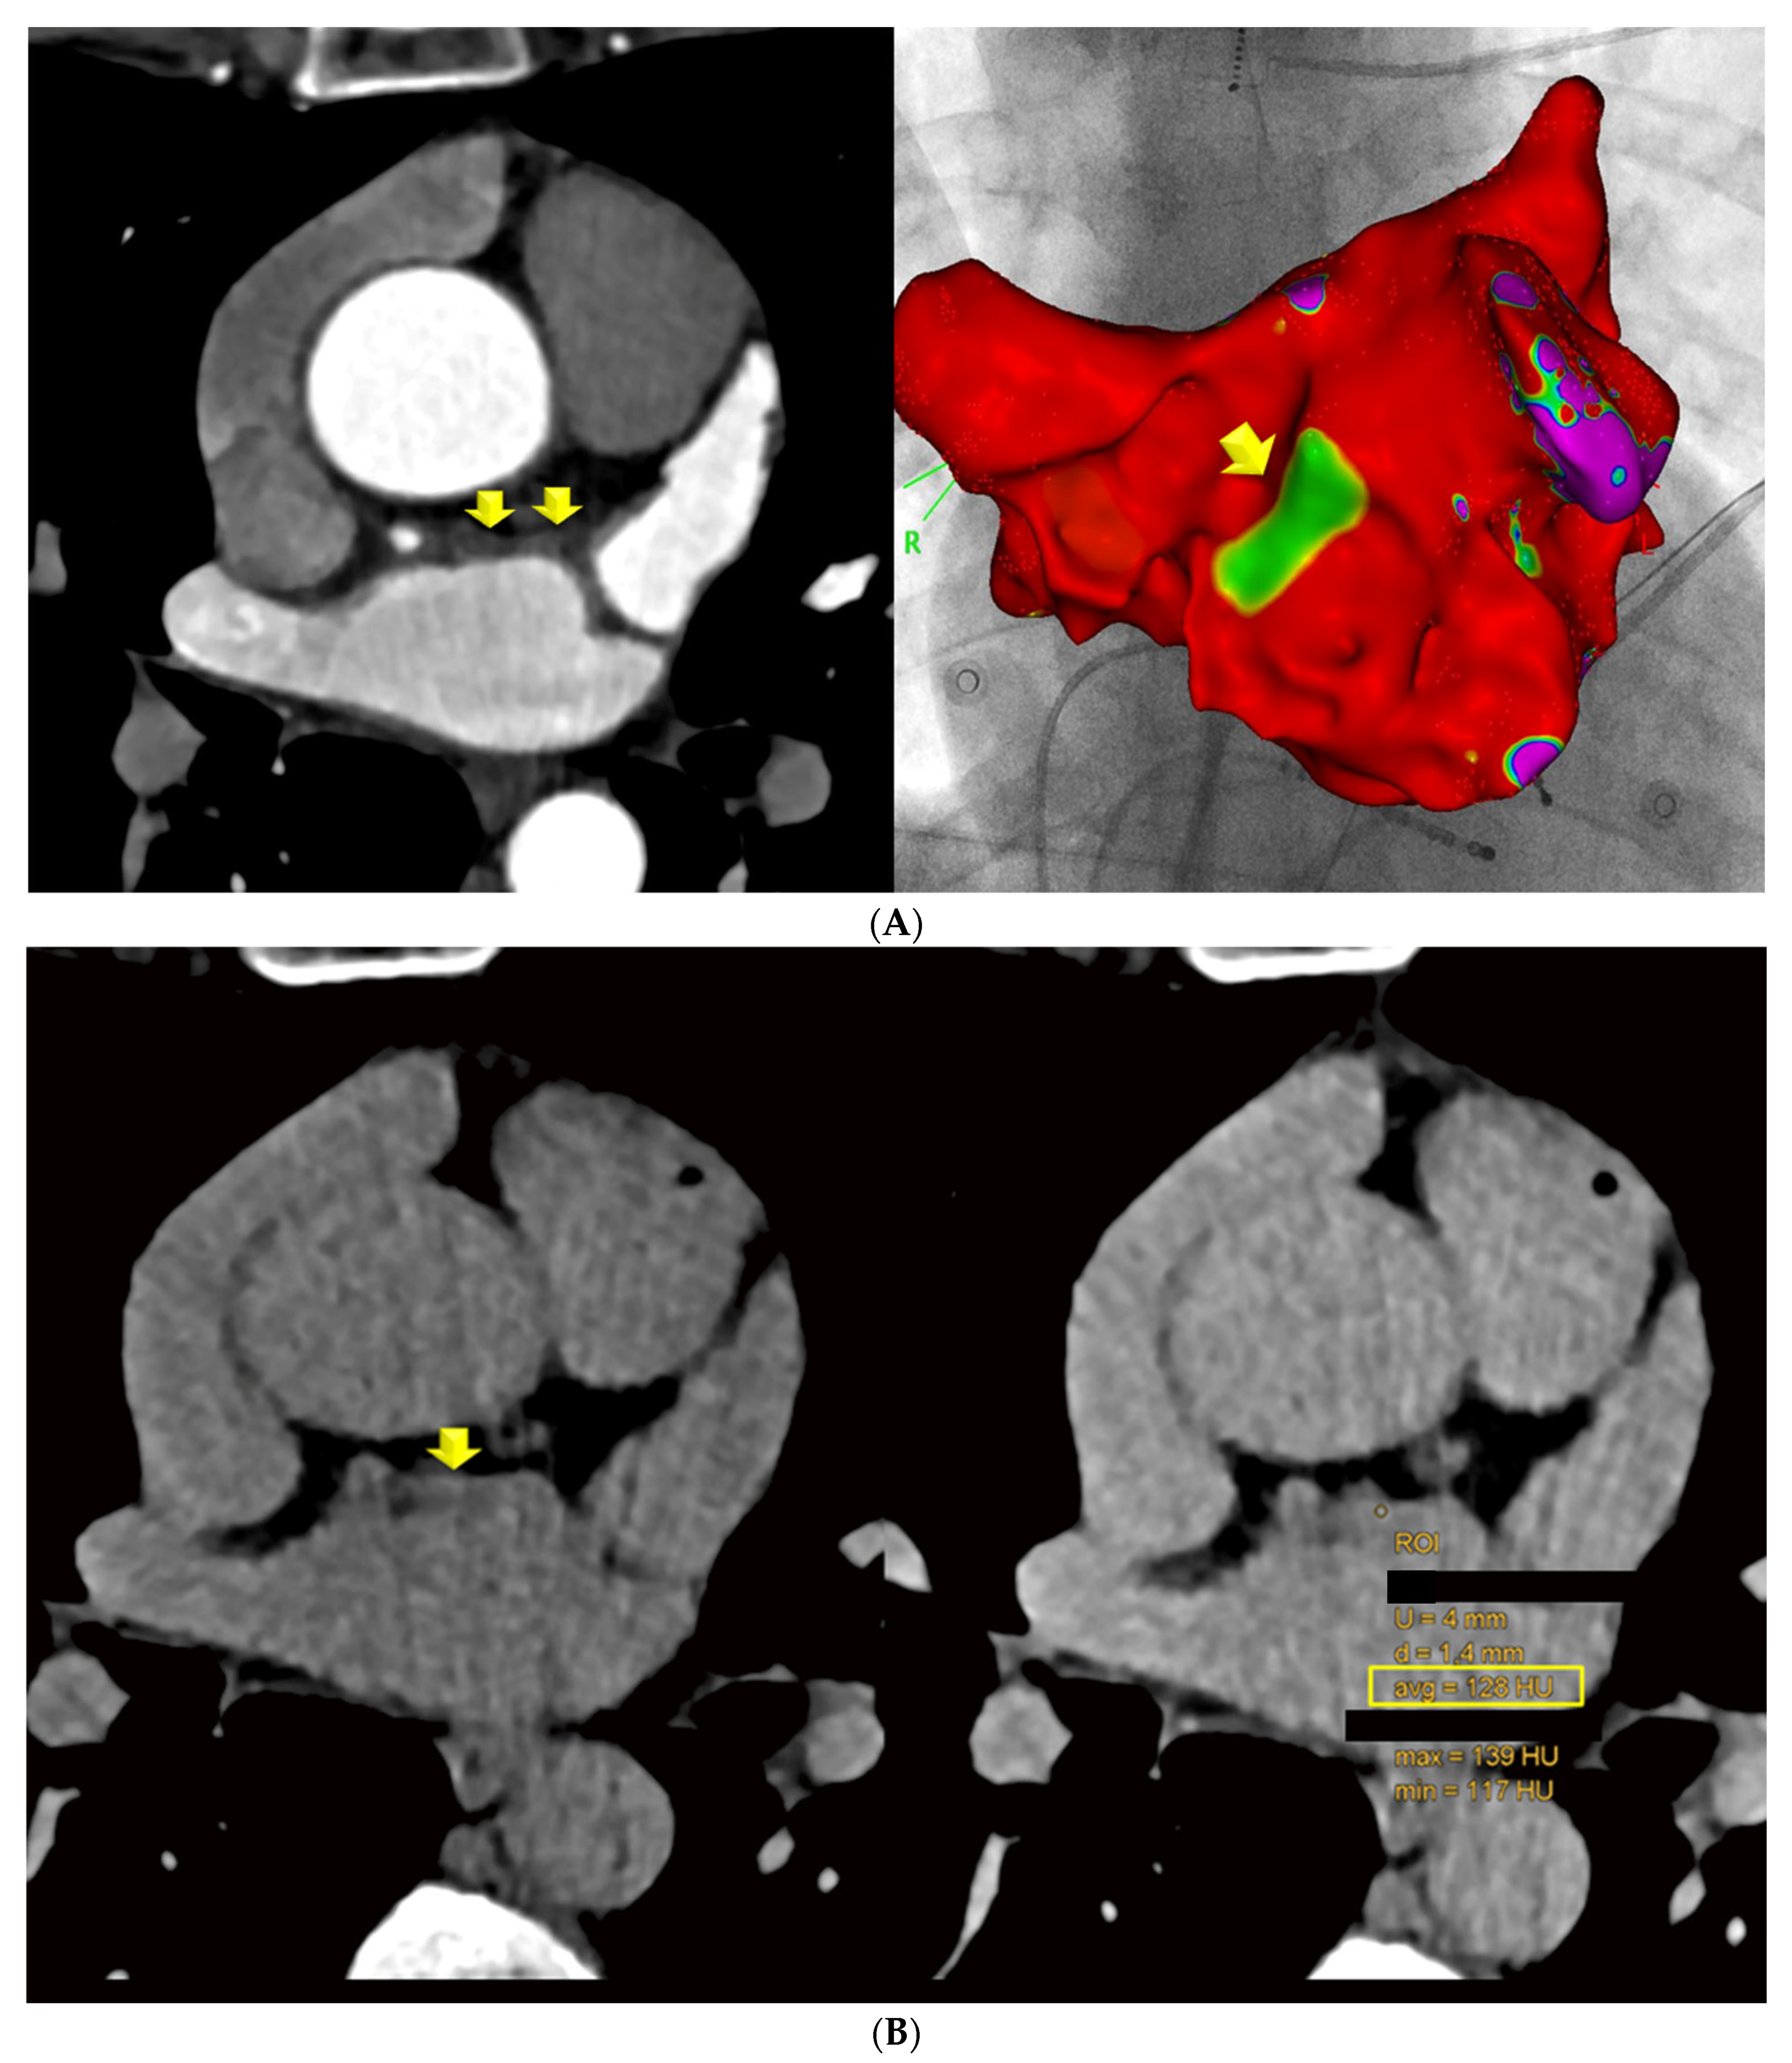

Late Enhancement Computed Tomography for Left Atrial Fibrosis Imaging: A Pilot “Proof-of-Concept” Study

2.2. Computed Tomography (CT)

2.3. Electroanatomical Mapping and Left Atrial Catheter Ablation